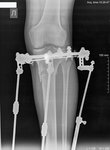

Исходник 38 лет. Алматы.

Дата операции 17.04.2018г.

Перед крутками!